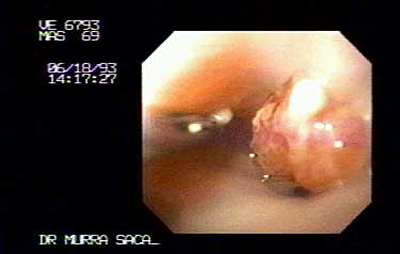

Imagen del cardias, Paciente Masculino 69 años:

Con disfagia progresiva, perdida de peso 20 libras y sialorrea, presenta Carcinoma del cardias y fondo, ver imagenes siguientes.